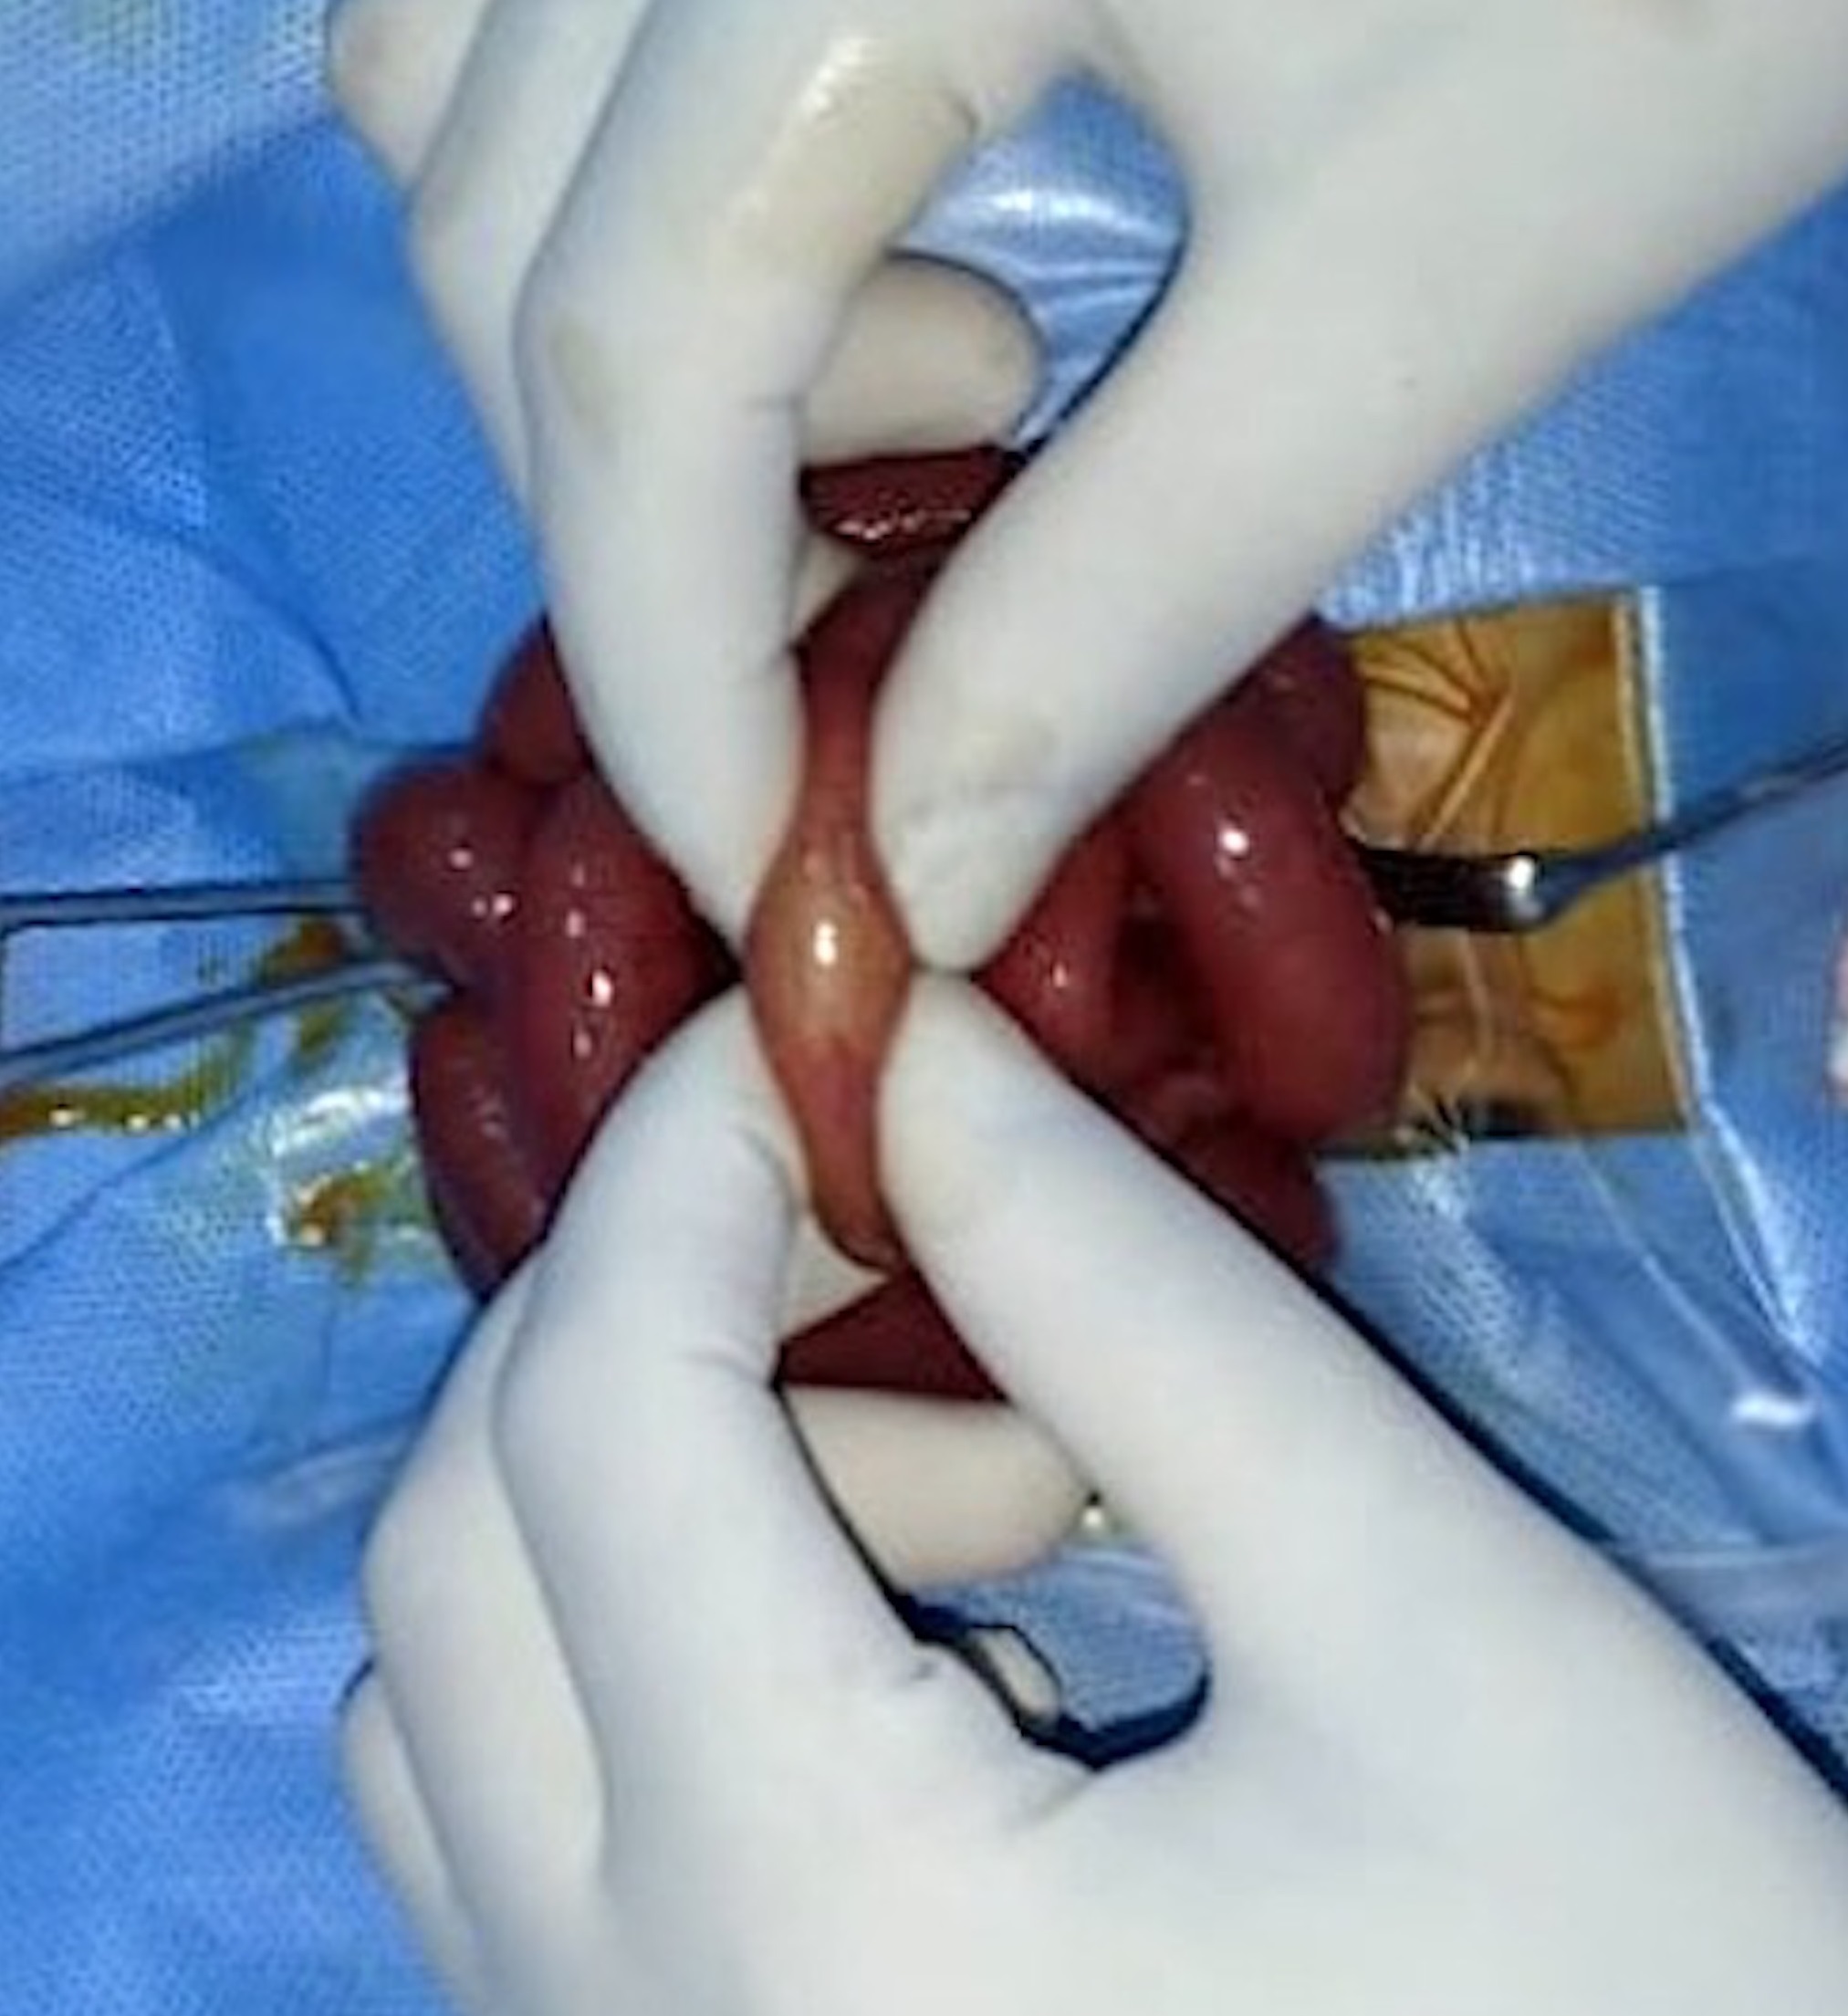

A diagnosis of intestinal obstruction was made; however, the clinical and radiological features did not point at any likely etiology. As the patient had acute intestinal obstruction, he was taken up for emergency exploratory laparotomy. The intraoperative findings showed dilated small bowel loops with an intraluminal soft, globular foreign body impacted in the distal ileum (Fig. 2). The bowel was opened longitudinally over the foreign body which was found to be a swollen raisin that had imbibed fluid and swollen up and was completely obstructing the narrow lumen of the terminal ileum (Fig. 3). The raisin was removed and the enterotomy was closed. On re-inquiry, it was found that the elder sister who was five years old, playfully put a raisin into the mouth of the newborn, which went unnoticed by the parents. Postoperative recovery was uneventful, and the patient was discharged in good clinical condition. The child was initially on 3 monthly follow up for one year. During the last follow-up, he was 2 years old, asymptomatic, and had normal developmental milestones.

Bezoars are rare in neonates. Based on their composition, they are classified into phytobezoars (concretions of vegetable matters), trichobezoars (hair), lactobezoar (concentrated milk formulas), pharmacobezoars (drugs), and food bolus bezoars. Phytobezoars are concretions of indigestible fibers derived from ingested vegetables and fruits. They have been ascribed to the ingestion of mainly persimmon, coconut fibers, celery, skin, and stems of grapes, prunes, raisins, leek, mallow, and wild beets.[22] The mechanism of phytobezoar formation from plant substances is probably mechanical and depends upon the insoluble and indigestible fiber content.[22] They are commoner in adults and rarely reported in the pediatric age group.[23] The most common site of formation is the stomach and it is not unusual to find parts of phytobezoar in the small bowel.[24] Primary small bowel phytobezoars are rare and are almost always obstructive. They usually become impacted in the narrowest portion of the small bowel, the commonest site being the terminal ileum followed by the jejunum. [25] In our patient, the raisin had gradually swollen up and got impacted in the terminal ileum causing the obstruction, which could be discovered only after an enterotomy.

Intraluminal soft globular foreign body impacted in the distal ileum.

Enterotomy revealing a swollen raisin impacted in the distal ileum.